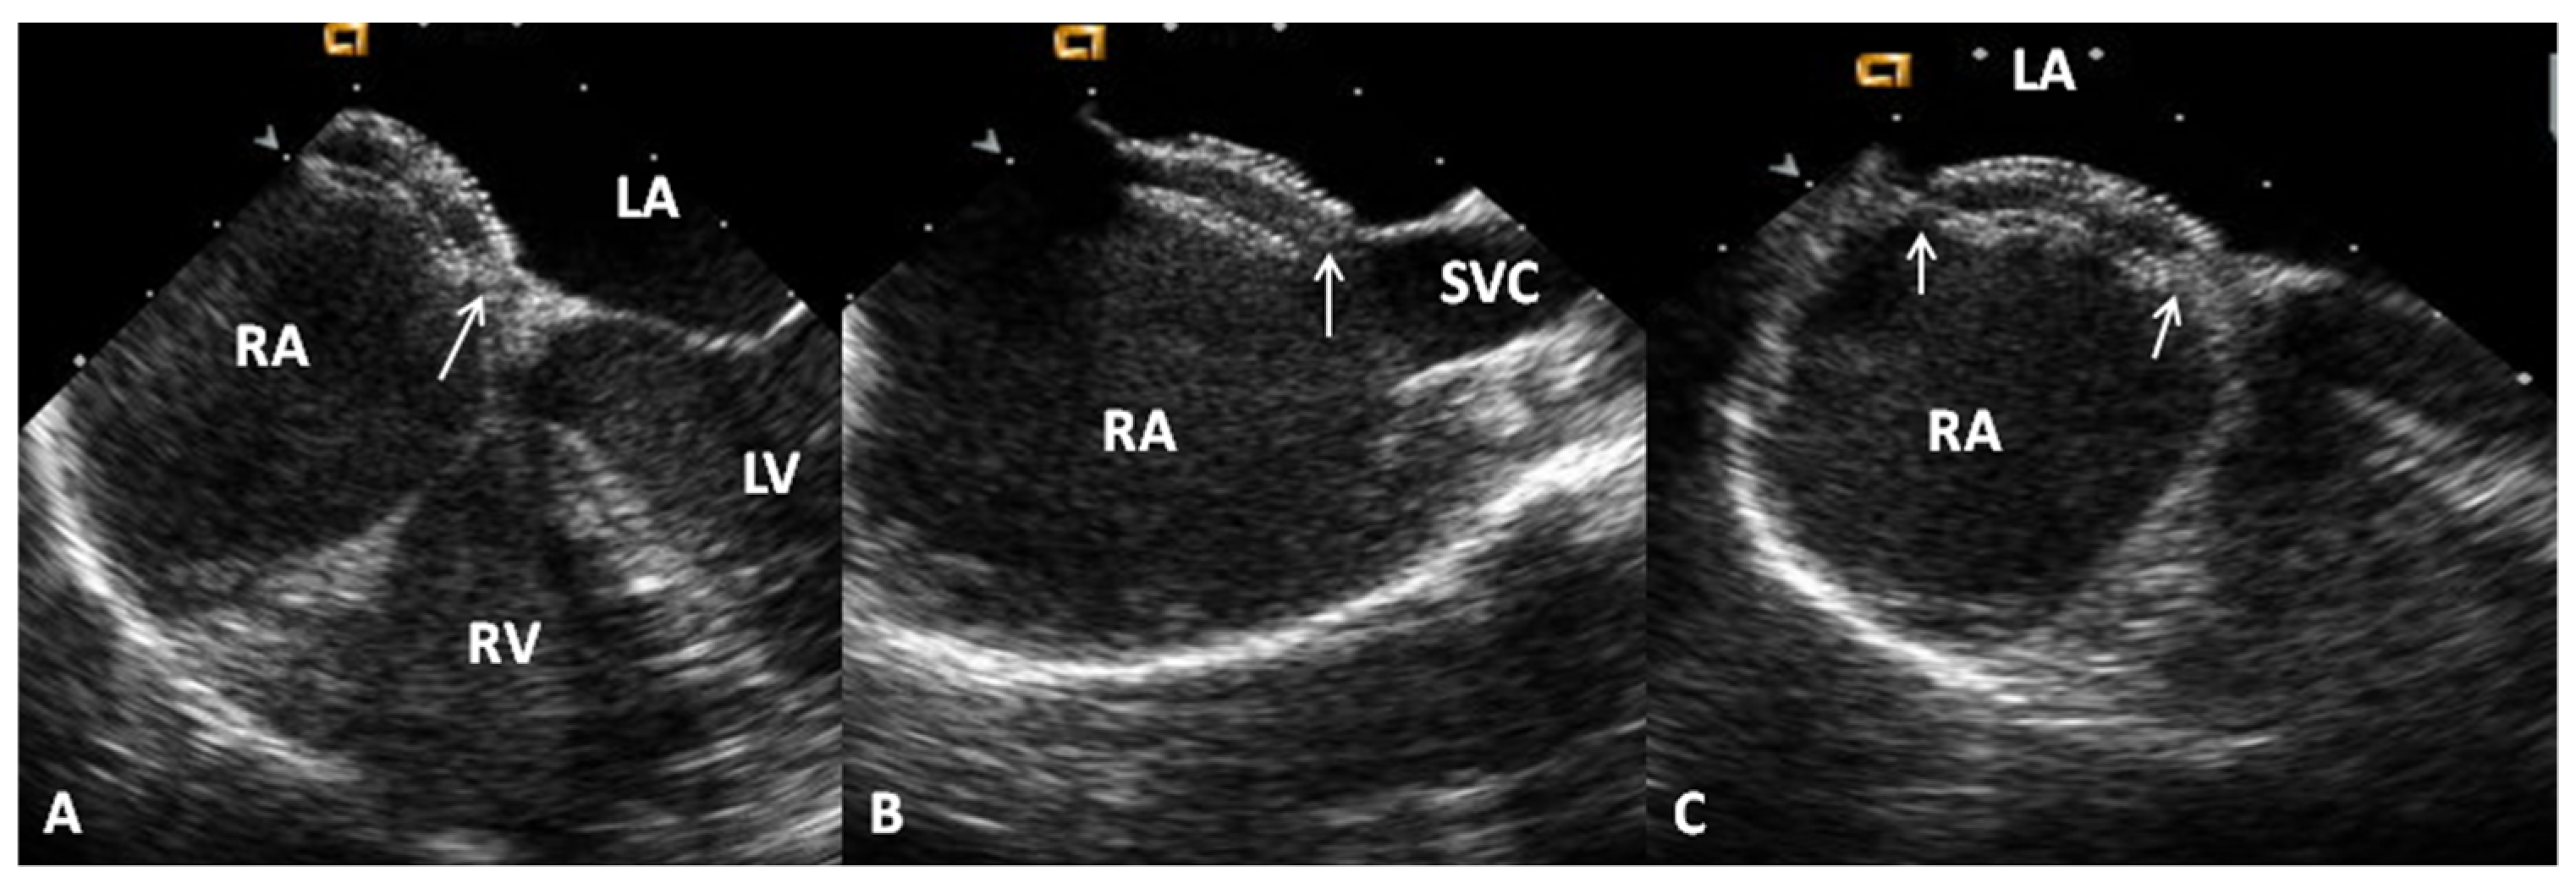

- Banerjee, A.; Bengur, A.R.; Li, J.S.; Homans, D.C.; Toher, C.; Bank, A.J.; Marx, G.R.; Rhodes, J.; Das, G.S. Echocardiographic characteristics of successful deployment of the Das Angel Wings atrial septal defect closure device: Initial multicenter experience in the United States. Am. J. Cardiol. 1999, 83, 1236–1241. [Google Scholar] [CrossRef]